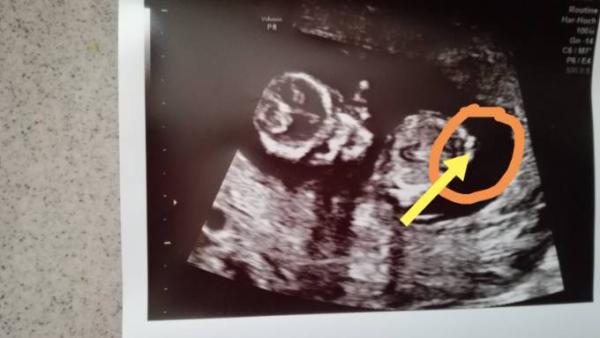

Hab den besagten Bereich jetzt mal markiert ;) Es ist ja eh egal was es wird, hab mich schon auf ein Geschlecht eingestellt aber bis zur Geburt bin ich halt ein Hobbydetektiv

Bild zu